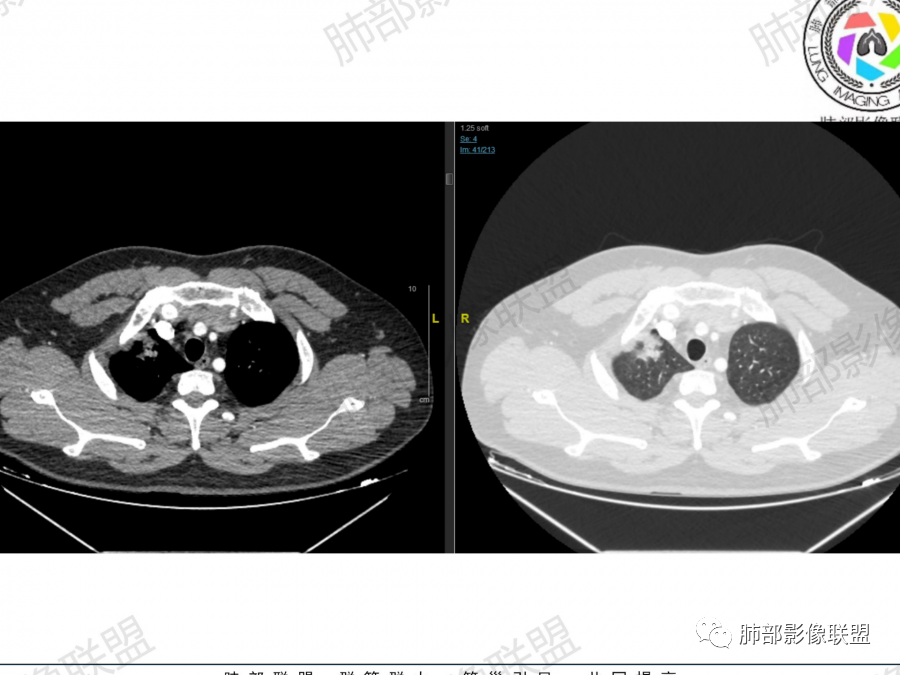

晨读:男,37岁,咳嗽气喘一月,加重两天。CT示右肺多发实变影,大者位于右肺上叶尖段,内可见空洞,局部内部可见残存肺组织,余结节位于胸膜下,强化均匀,内部可见血管穿行。首先考虑隐球菌感染可能,其次淋巴增殖类疾病

晨读:青年男性。咳嗽气喘1月,胸部ct:右肺多发结节、肿块,沿着支气管血管束及胸膜下分布,边缘平直,清楚,内支气管基本通畅、轻微扩张,血管走形自然。考虑淋巴增殖性病变,淋巴瘤?注意鉴别血管炎、隐球菌病。

典型,青年男性,有铁蛋白增高,有免疫异常,胸膜下,长轴平行胸膜,病灶内血管走行自然。

青年人,没有纵隔淋巴结肿大,没有肝脾肿大,没有发热,尽量不要轻易考虑淋巴瘤

青年人的淋巴瘤一般都是HD更多见,纵隔和其他地方淋巴结肿大明显,肝脾肿大明显

多发结节或实变型:分布多为下叶单叶胸膜下、少数两肺多发、多叶段分布。弥漫型:本例为单侧肺、多叶结节型。

2、隐球菌感染有时相性,初期的隐球菌感染周围有晕征,晕从多变少,或包裹,或吸收,结节实性区可迅速变大,后期(慢性期)的隐球菌周围无明显晕征,边界较清楚。本例病变发病一月, 为后期,晕征不明显。